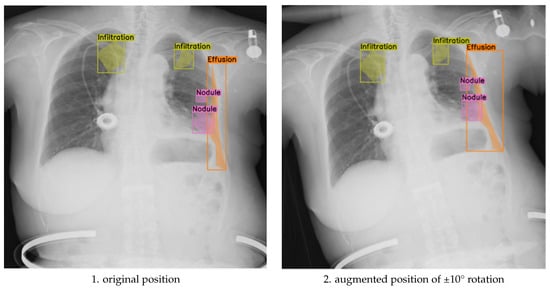

The purpose of this ablation design was to evaluate whether small-angle geometric rotation, when applied in conjunction with clinically constrained augmentation, contributes to measurable gains in segmentation precision and generalization. Previous studies often apply compound augmentations without considering their impact on anatomical alignment or label consistency. In contrast, our approach isolates the effect of rotation magnitude within a robust, expert-validated augmentation framework. This ensures that any observed performance differences can be attributed primarily to rotation, rather than to uncontrolled variation in other augmentation parameters. As illustrated in Figure 3, applying ±10° rotations introduces noticeable shifts in the spatial distribution of segmented pathologies, such as infiltration, effusion, and nodules, demonstrating that larger angular deviations can alter anatomical context and impact the alignment between pathological features and image landmarks.

Figure 3.

Comparison of original and discrete rotations at (−10°, +10°) augmented chest X-ray images.

These results underscore the nuanced impact of augmentation magnitude: while ±10° rotations contribute broader positional diversity, they carry a higher risk of annotation drift. In contrast, ±5° rotations offer a controlled variability that strengthens the model’s sensitivity to subtle abnormalities without sacrificing spatial coherence. The optimal augmentation strategy depends on clinical priorities, robustness to extreme imaging conditions versus precision in fine-grained abnormality detection, and may benefit from a hybrid approach that combines both rotation levels in training.